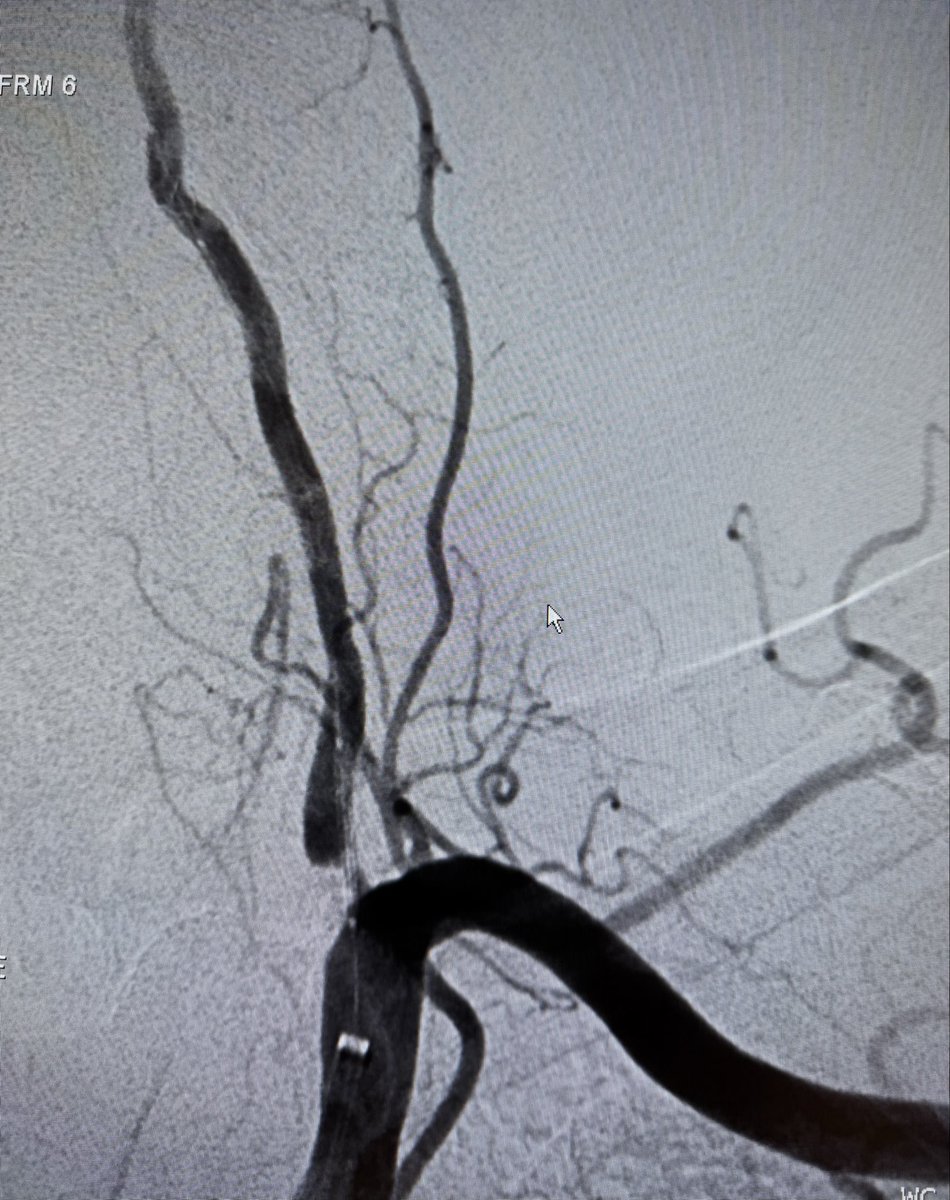

Partial disassembly at the junction to expose the internal stiff wire lets you manually control the lever and free a stuck Perclose footplate—turning a stressful moment into a controlled one. Practical, reproducible, and worth remembering.